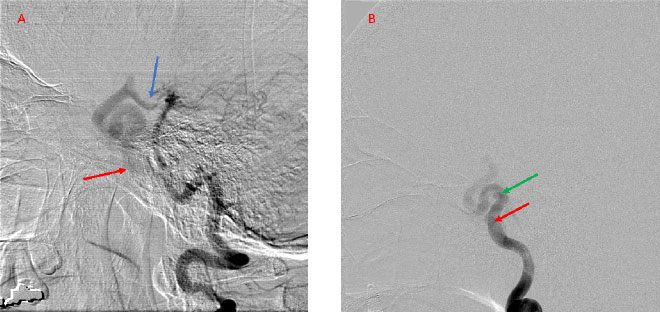

A 55-year-old woman presented with acute onset of severe headache, and possible witnessed seizure. Imaging confirmed intraventricular hemorrhage primarily focused within the fourth ventricle with diffuse […]